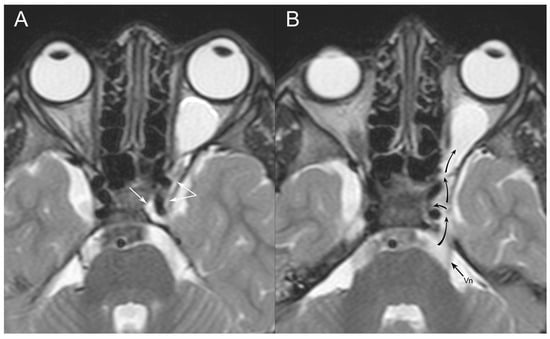

3.1. Case Report